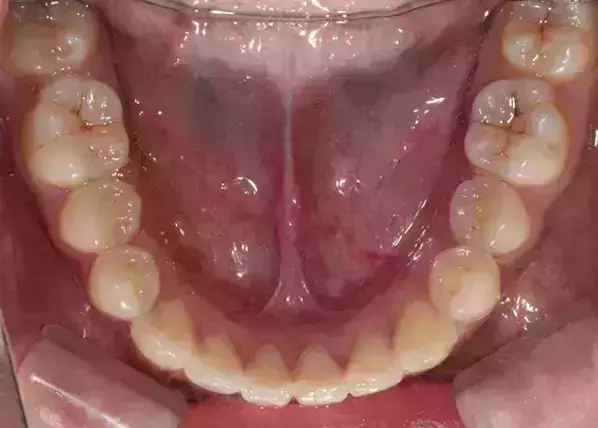

Damon 病例分享:安氏 II 類(lèi)二分類(lèi)露齦笑的矯治(董一磊)

患者信息